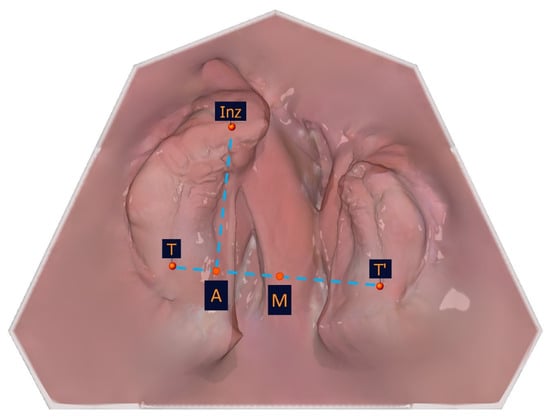

To identify the transversal landmarks, the large and small segments were divided into the subsegments (T-C2, C2-Inz, and Inz-P1 for the large segment and P2-C2′ and C2′-T′ for the small segment). The most vestibular and most palatal points in each section were determined (Table 2, Figure 5).

Figure 5. Illustration of the segmental width measuring measurement points of the partial jaw segments. The segmental width measurement points and their description are presented in Table 2.